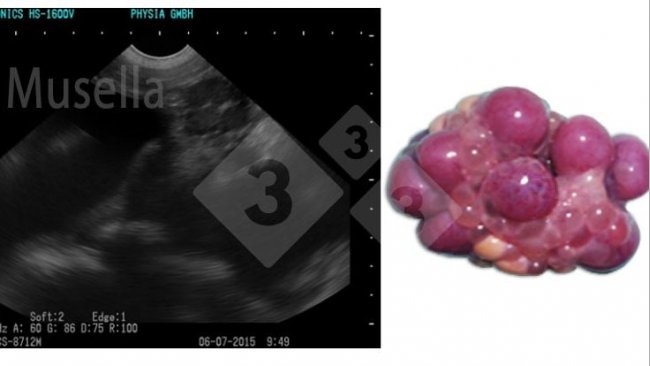

Oto jak ultradźwięki mogą być wykorzystywane do wizualizacji struktur jajników, oceny stanu dojrzewania i diagnozowania patologii jajników.